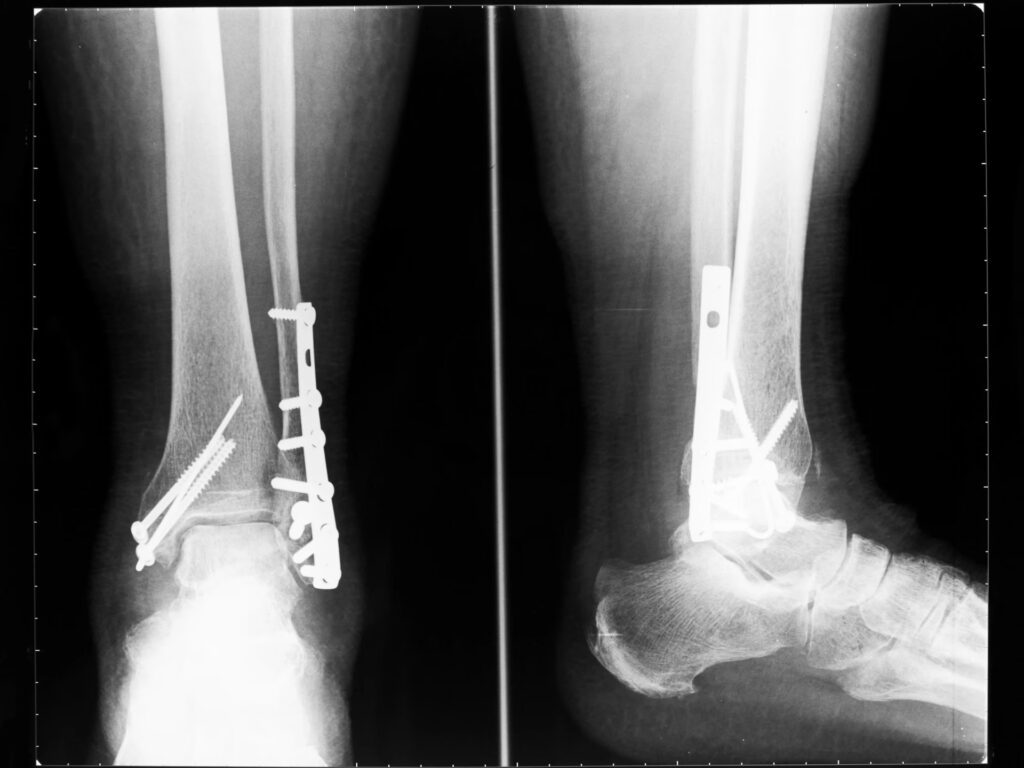

Under operationen vil kirurgen implantere metalplader, stænger eller skruer for at holde knoglestykkerne i den korrekte position under helingen. Ved et brud på lårbenet (femur) er den mest almindelige operation at indsætte en lang metalstang (marvsøm) ned gennem midten af knoglen for at stabilisere den indefra. I andre tilfælde kan en ekstern fiksationsramme anvendes, hvor metalpinde føres gennem huden ind i knoglen og fastgøres til en ramme uden på benet. Denne ramme giver stabilitet og fjernes typisk efter 6-8 uger.

Skal metalplader og skruer fra en operation fjernes igen?

I mange tilfælde bliver implantaterne siddende permanent i kroppen uden at give problemer. De fjernes kun, hvis de forårsager smerte, irritation eller andre komplikationer. Dette er en beslutning, du vil træffe i samråd med din ortopædkirurg.